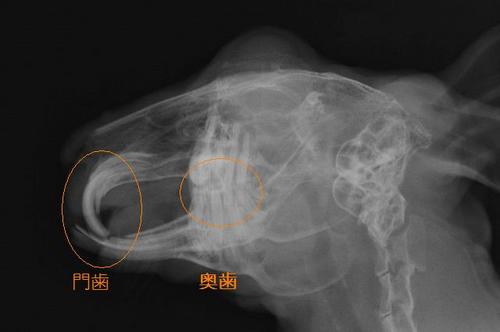

写真は門歯の噛み合わせが悪くなったウサギの横から見たレントゲン写真です。

門歯のすり減り方の異常と、奥歯が伸びすぎている様子です。 Img5933-2.jpg